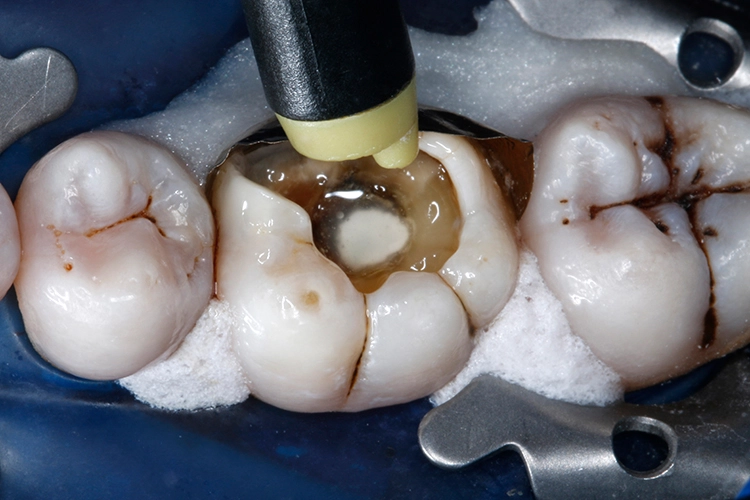

Im nächsten Schritt wurde das thermoviskose Komposit VisCalor (VOCO) im VisCalor Dispenser (VOCO) auf 65 °C erwärmt (Abb. 17). Die schmale, biegsame Kanüle der VisCalor Kompule erleichtert eine direkte Applikation auch in schwer zugängliche Bereiche und enge Kavitätenareale (Abb. 18). Die Kavität wurde mit dem ersten 2-mm-Inkrement bis ca. zur Hälfte der Defekthöhe aufgefüllt.

Durch die niedrigviskose Konsistenz im erwärmten Zustand resultiert ein hervorragendes Anfließverhalten an die Kavitätenwände (Abb. 19). Die 1. Kompositschicht wurde für 10 Sek. mit einer Polymerisationslampe (Lichtintensität ≥ 1.000 mW/cm²) ausgehärtet (Abb. 20).